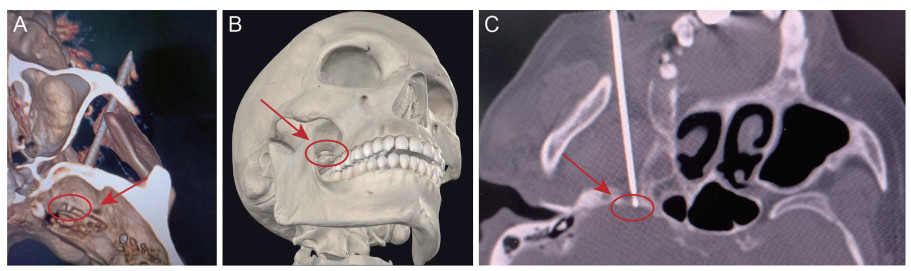

Utilization of three-dimensional anatomy software in the standardized training curriculum for the pain department

WENG Lijun, WANG Yaguang, SHENG Kui, XIANG Jiao, BAO Lijun, WANG Jiayou

2025, 23(11): 1950-1953. doi: 10.16766/j.cnki.issn.1674-4152.004267

1429 4

Abstract:

Objective  To investigate the application effects of three-dimensional anatomy software in standardized training and educational practices within the field of pain medicine, and to verify its superiority in improving the anatomical knowledge and surgical skills of resident doctors through comparative analysis.  Methods  Sixty resident doctors with no fundamental understanding of pain medicine from the Department of Pain Medicine at the Second Affiliated Hospital of Anhui Medical University from January 2020 to December 2022 were selected and randomly divided into a software teaching group and a conventional teaching group by drawing lots, each consisting of 30 students. The software teaching group utilized three-dimensional anatomy software combined with case-based teaching methodologies, while the conventional teaching group used radiological imaging data in conjunction with traditional multimedia teaching techniques. After the course, the instructional efficacy was assessed through theoretical evaluations (covering aspects such as trigeminal nerve anatomy, pathway, branches and distribution, typical clinical symptoms, causes, common treatment methods, and prognosis of trigeminal neuralgia) and surveys.  Results  The statistical analysis of the theoretical examination results revealed that students in the software teaching group achieved significantly higher scores compared to those in the traditional teaching group (Z=-5.388, P < 0.001). Furthermore, the findings of the questionnaire survey indicated that the software teaching group exhibited significantly greater proficiency in anatomical structure mastery (t=8.042, P < 0.001), clinical diagnosis and treatment level enhancement (t=8.625, P < 0.001), and cultivation of learning interest (t=10.522, P < 0.001) compared to the traditional teaching group.  Conclusion  The combination of three-dimensional anatomy software and case-based teaching not only significantly improves the theoretical assessment scores of pain medicine resident doctors but also effectively enhances the satisfaction and interest of students in learning. It is of great significance for promoting students ' in-depth understanding of complex regional anatomy, stimulating enthusiasm for learning, and building confidence, thus facilitating a smoother transition to becoming a pain medicine physician.